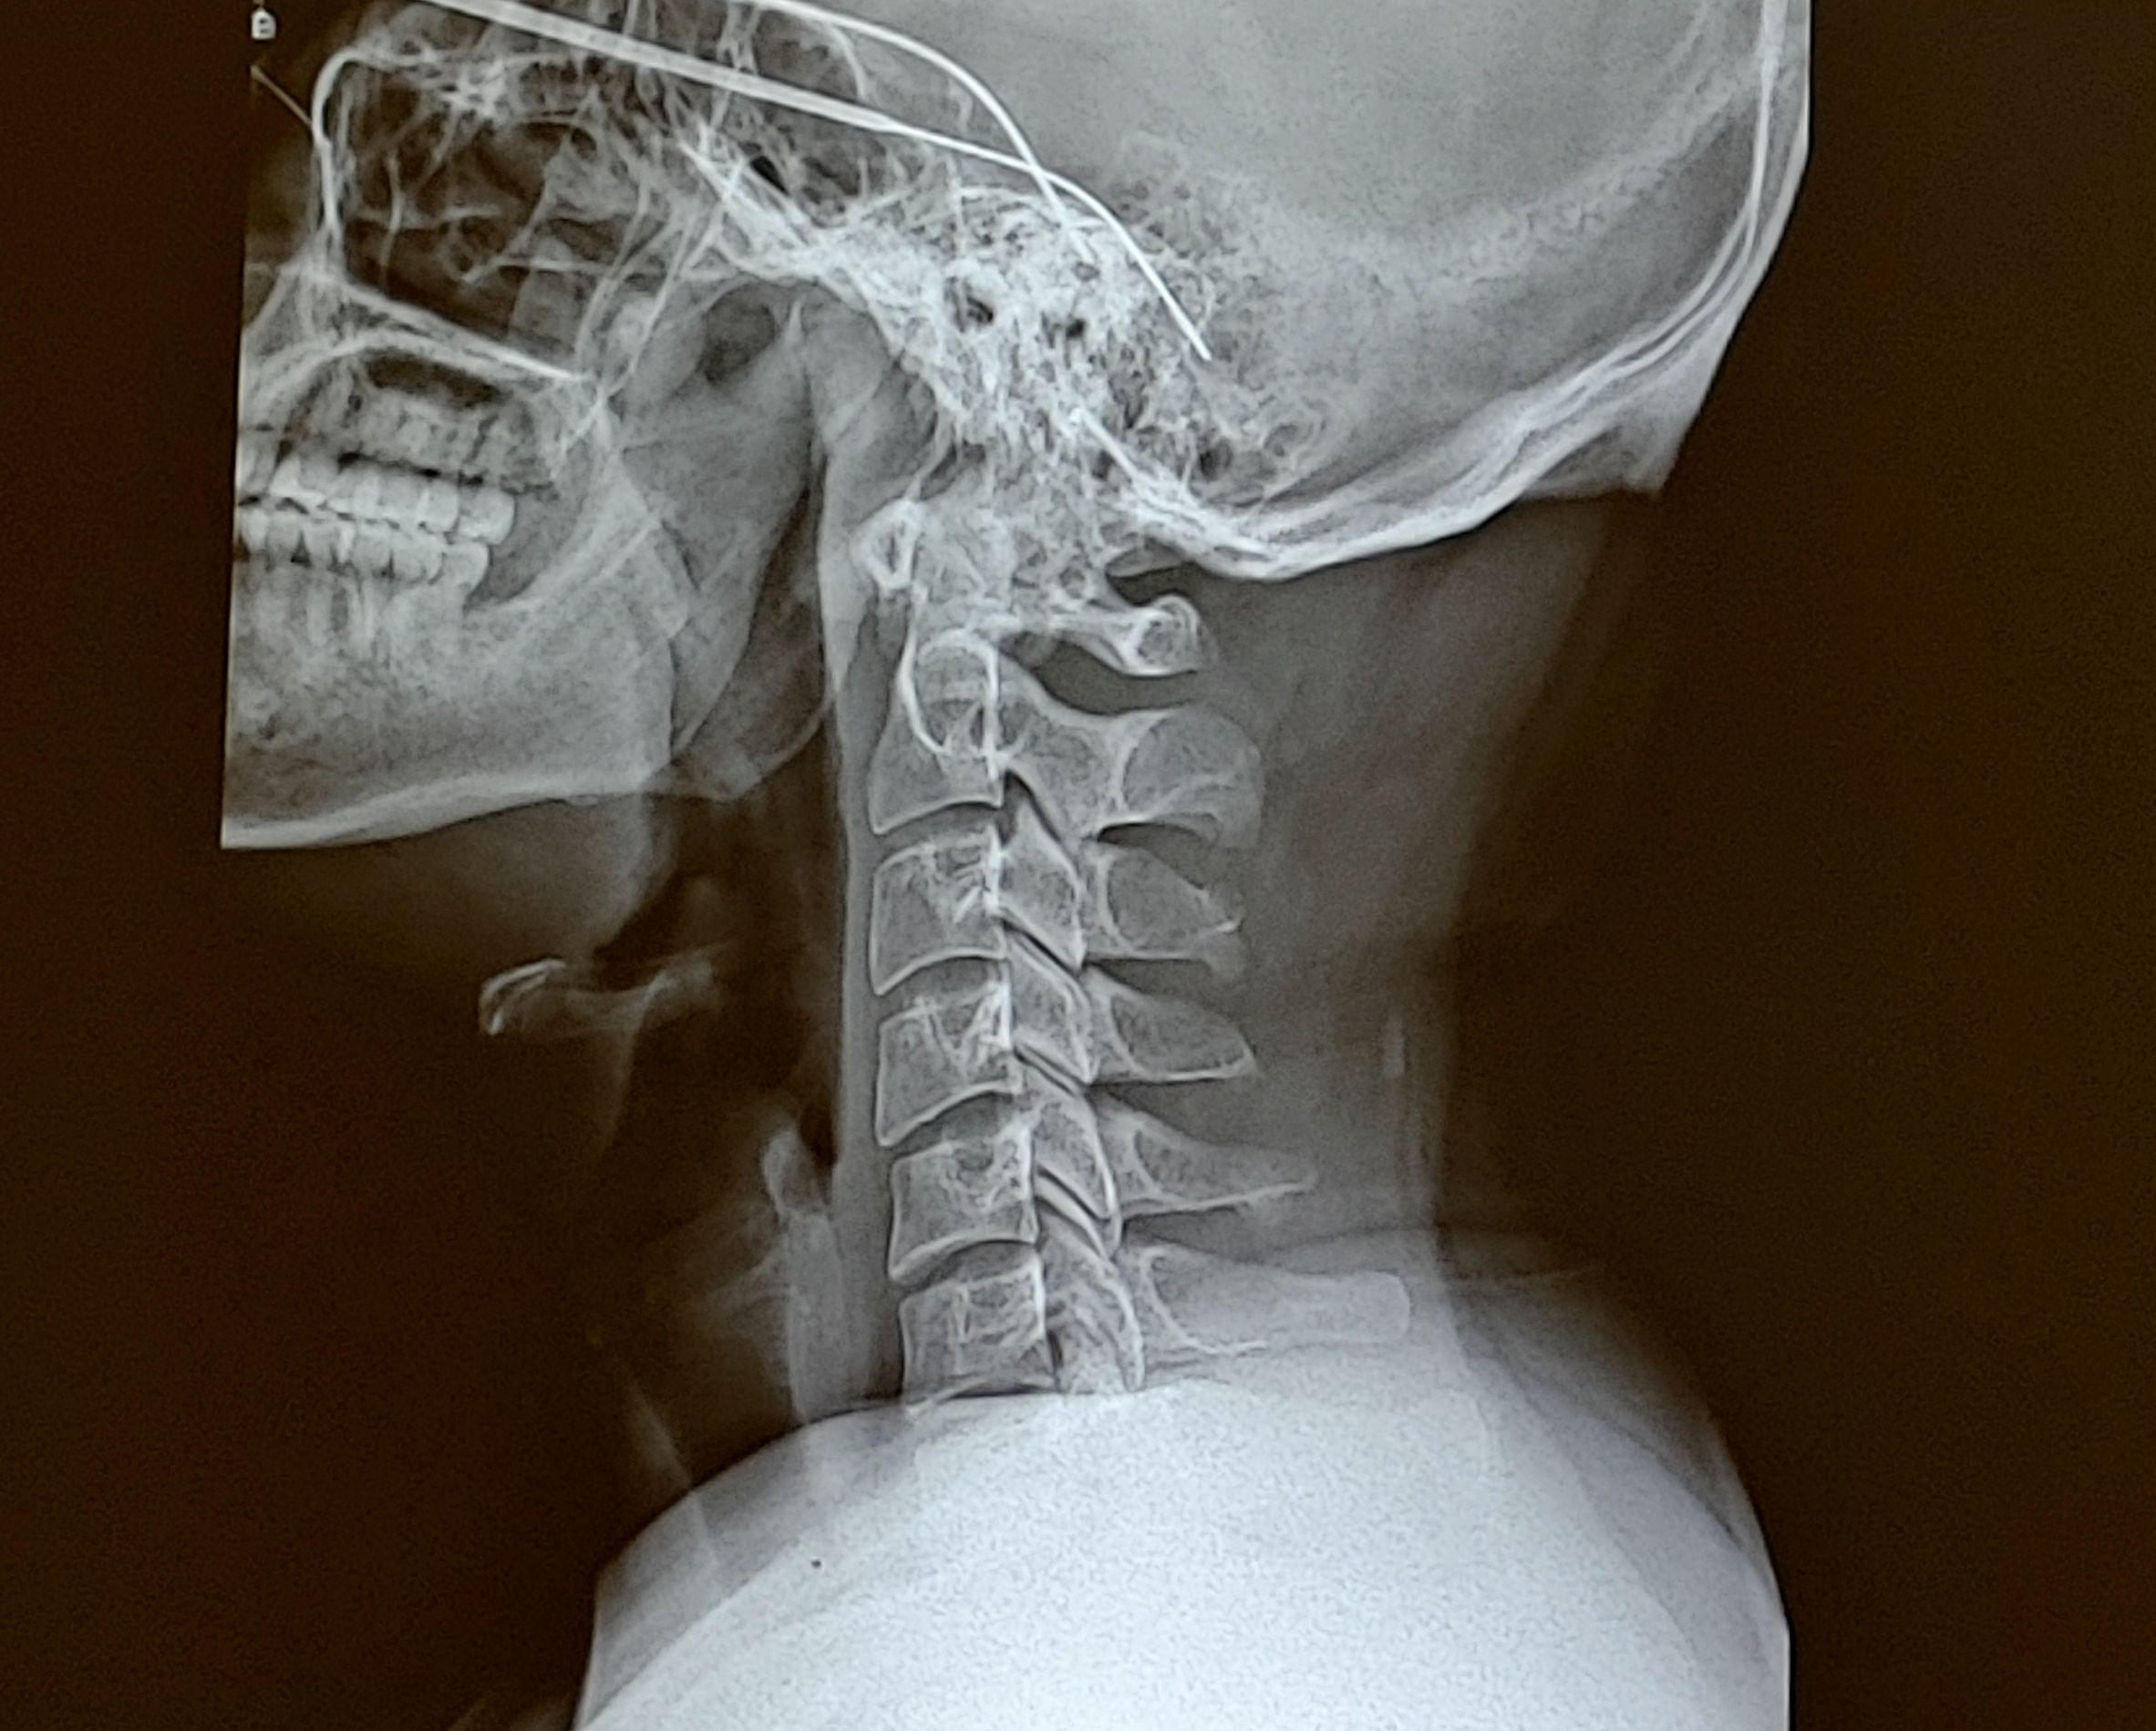

거북목과 일자목은 그 중 하나로써 목에 생기는 질병입니다.

컴퓨터 화면을 자세히 보기 위해 고개를 내밀어 들여다 본다든가,

핸드폰의 작은 화면을 들여보 보기 위해 고개를 숙인하든가 하는 것이

장시간 이어질 경우 근육, 뼈 등 신체의 변형으로 이어집니다.

외견상으로 보기 안 좋아지는 것이 물론이고,

심해지면 통증까지 동반하여 일상 생활에 큰 지장을 줄 수 있습니다.